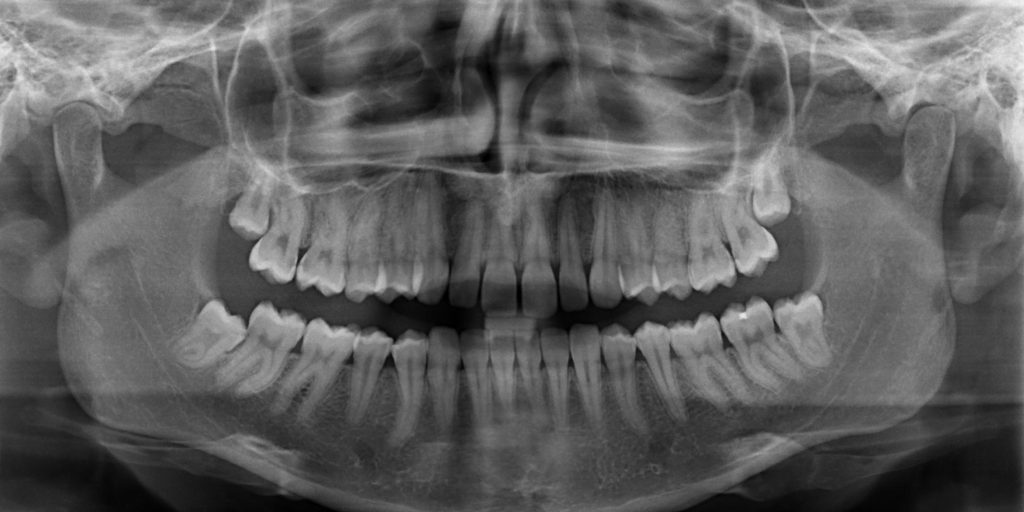

Eine der wichtigsten Untersuchungsmethoden des Zahnarztes ist schon seit Jahrzehnten das Röntgen. Das entstehende Röntgenbild zeigt die innere Beschaffenheit der Zähnen und der Kiefer. Es hilft somit bei der Erstellung von Diagnosen und ist für die Behandlungsplanung eine wichtige Voraussetzung. Je nach Fragestellung kann ein digitales Röntgen von einzelnen Zähnen und begrenzten Kieferbereichen, aber auch eine umfassende, so genannte Panoramaaufnahme (ein OPG) angefertigt werden.

Das Erstellen einer Röntgenbildes dient beispielsweise der Diagnose von Erkrankungen des Zahnhalteapparates, Frakturen von Zahn und Kiefer, Entzündungen, Neoplasien, der frühzeitigen Erkennung von Nichtanlagen, verlagerten und retinierten Zähnen sowie der Erkennung von Karies. Da in vielen Fällen die Oberfläche der Zähne glatt ist und der Zahnschmelz auf den ersten Blick intakt scheint, ist ein Teil der beginnenden Karies für den Zahnarzt nur im Röntgenbild erkennbar.